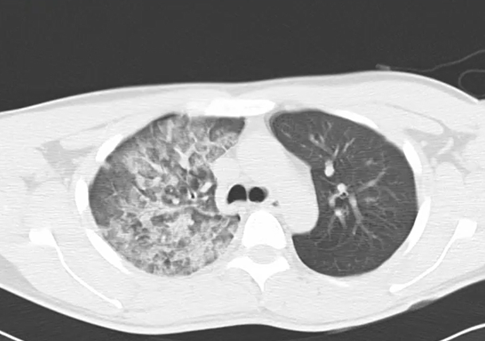

CTでは気胸は改善するものの浸潤影やすりガラス陰影